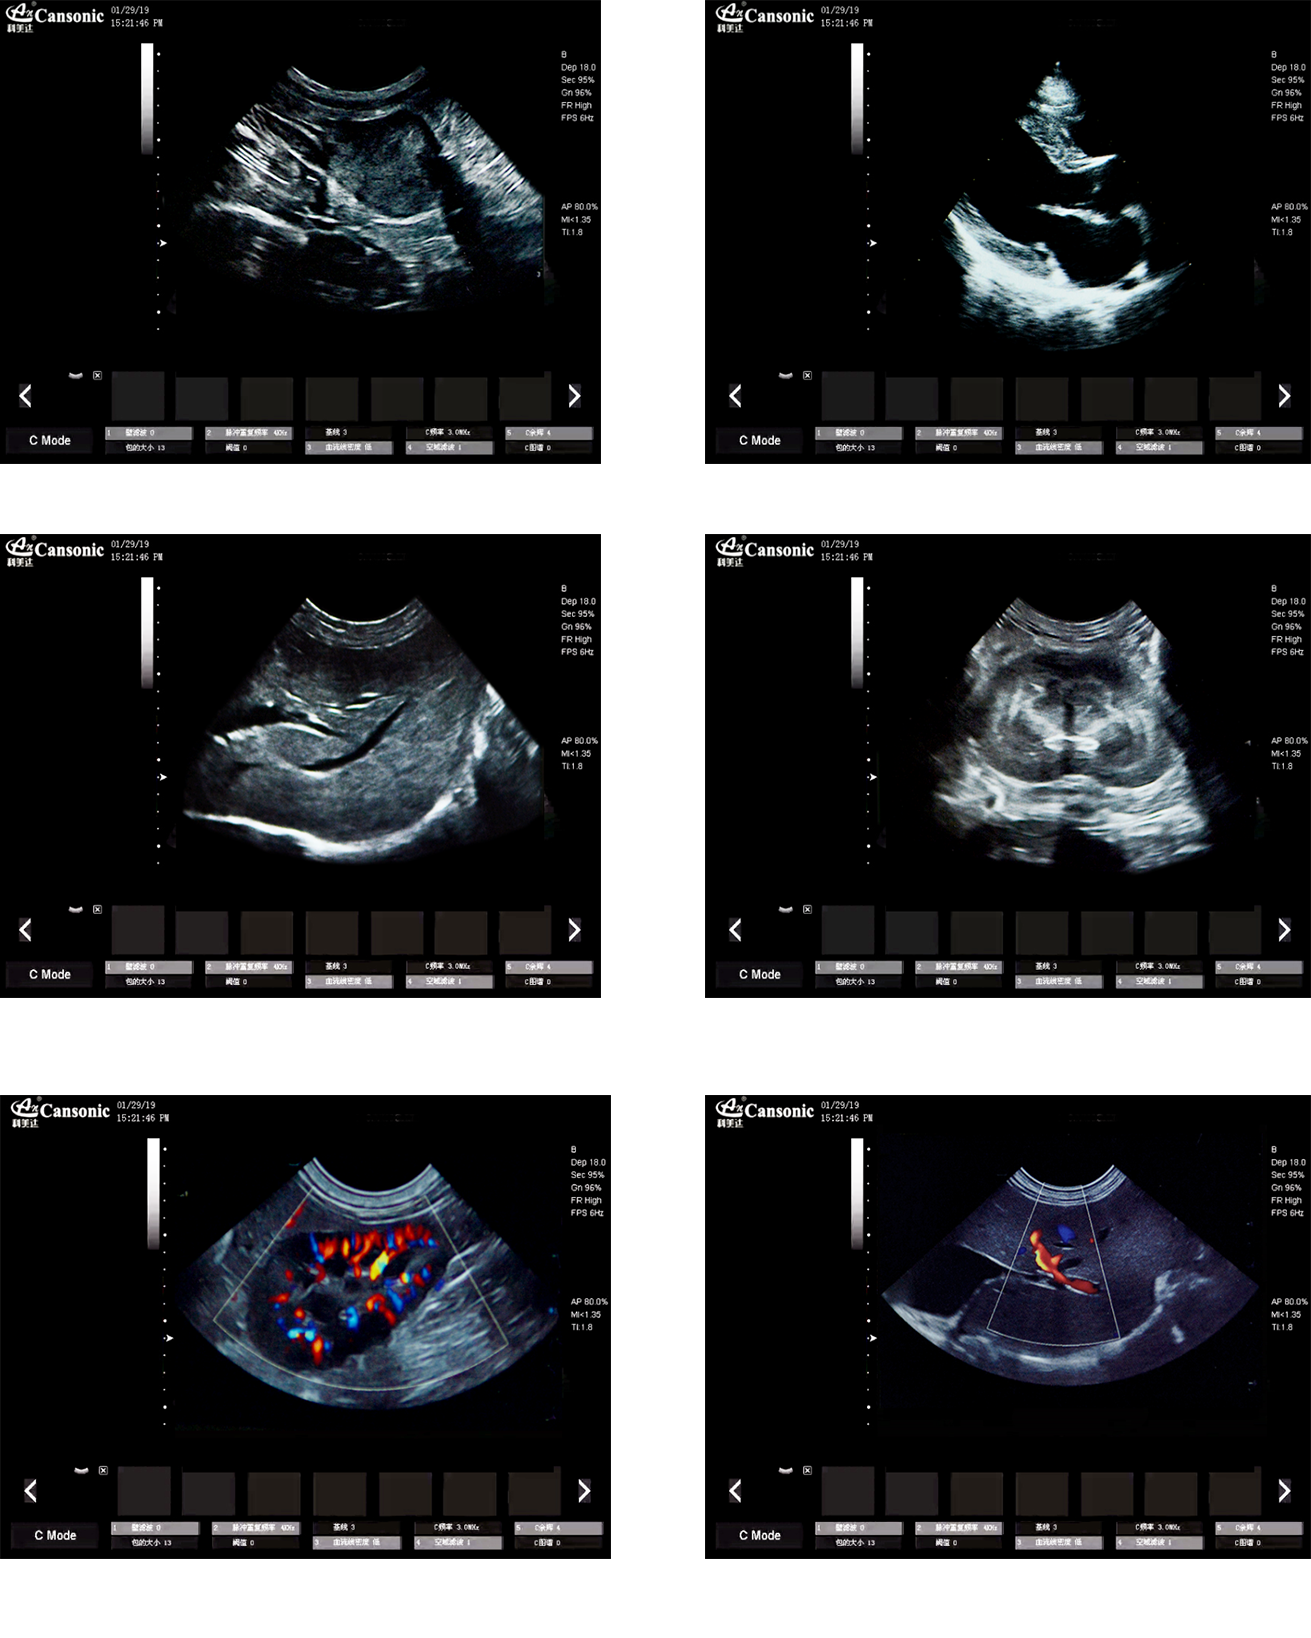

臨床圖示

1、薈萃高端彩超的專業(yè)技術,各類型的專業(yè)獸用探頭,提供完整的動物臨床診療方案

2、專業(yè)的獸用彩超軟件,適合犬、貓、馬、牛、羊等各類大小動物彩超檢查

3、完備的獸用高端功能,能量多普勒POWER模式彩色多普勒Color成像模式